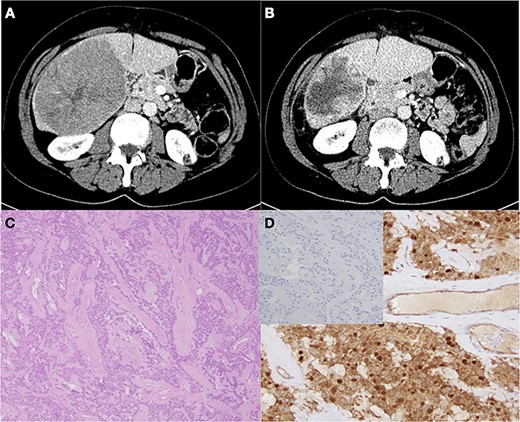

CT imaging of metastatic recurrent SPNP in right hepatic lobe before (A) and after (B) Y-90 treatment. (C) Characteristic pseudopapillae with hyaline stroma (H&E staining, ×4 magnification). (D) Confirmatory β-catenin immunostaining with negative chromogranin A staining (inset)

She presented again in November 2018 with a 3-month history of progressive right upper quadrant abdominal pain. Computed tomography (CT) imaging revealed a large hypoattenuating 10.3 × 12.7 × 9.8 cm3 lesion in the right hemi-liver, with multiple satellite lesions (Fig. 1A). There was no radiographic evidence of vascular invasion but extensive portocaval lymphadenopathy was noted. Liver core needle biopsy was consistent with recurrent solid pseudopapillary neoplasm. After a multidisciplinary discussion, it was recommended that she undergo Yttrium-90 selective internal radiation therapy (Y-90 SIRT) prior to resection and she received 118.4 Gy of treatment dose from a single administration of Theraspheres in January 2019. Posttreatment surveillance imaging in April revealed a remarkable interval decrease in size of the dominant mass to 8.3 × 6.4 × 7.1 cm3 without identification of any new lesions and stable lymphadenopathy (Fig. 1B). Given the favorable response to SIRT, long progression free interval and her excellent clinical status, an open extended right hepatectomy and portocaval as well as left renal vein lymphadenectomy were performed. Notably, extensive sclerosis and fibrotic reaction secondary to the Y-90 treatment made the portal dissection more challenging, but very accomplishable. She tolerated the procedure well and after a week in hospital was discharged home. Final pathology was consistent with multifocal solid pseudopapillary tumor, with negative margins and no evidence of tumor cells in the lymph nodes examined (Fig. 1C,D). There was visible treatment response with 50% residual tumor viability. She remains symptom free without any evidence of residual or recurrent disease.